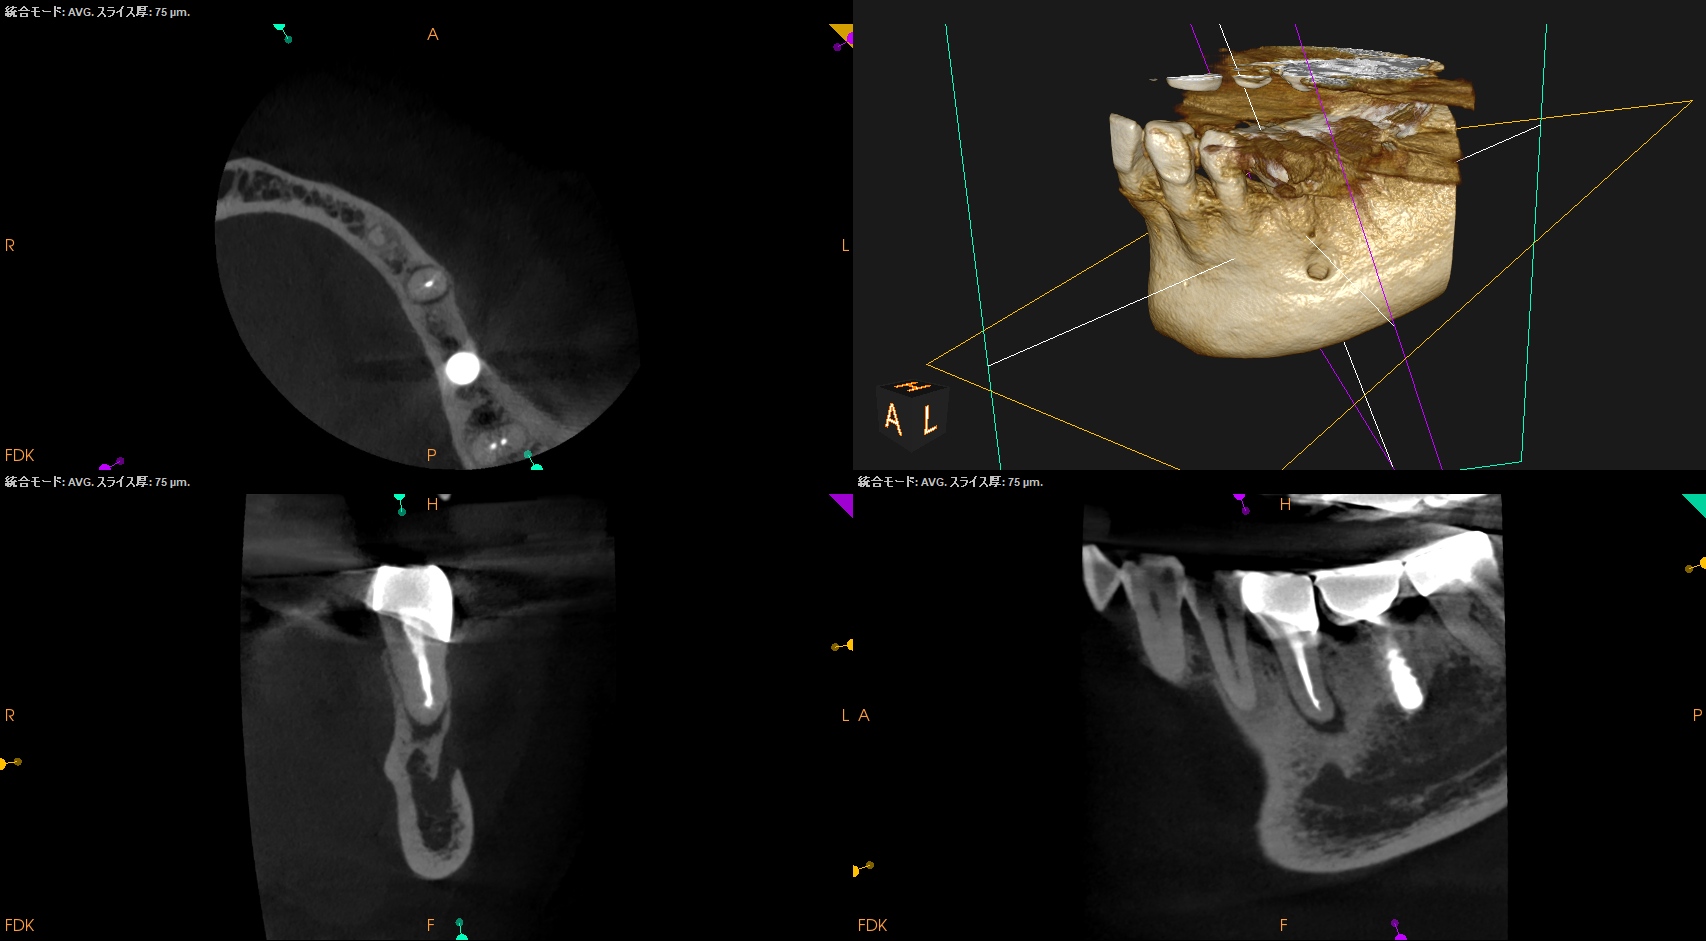

では、CBCTではどうだろうか?

そう。

Apicoectomyは不可能だ。

オトガイ孔を傷つけるリスクがあるからだ。

この瞬間に、

依頼された治療はApicoectomyからRe-RCT/Intentional ReplantationへChangeする。